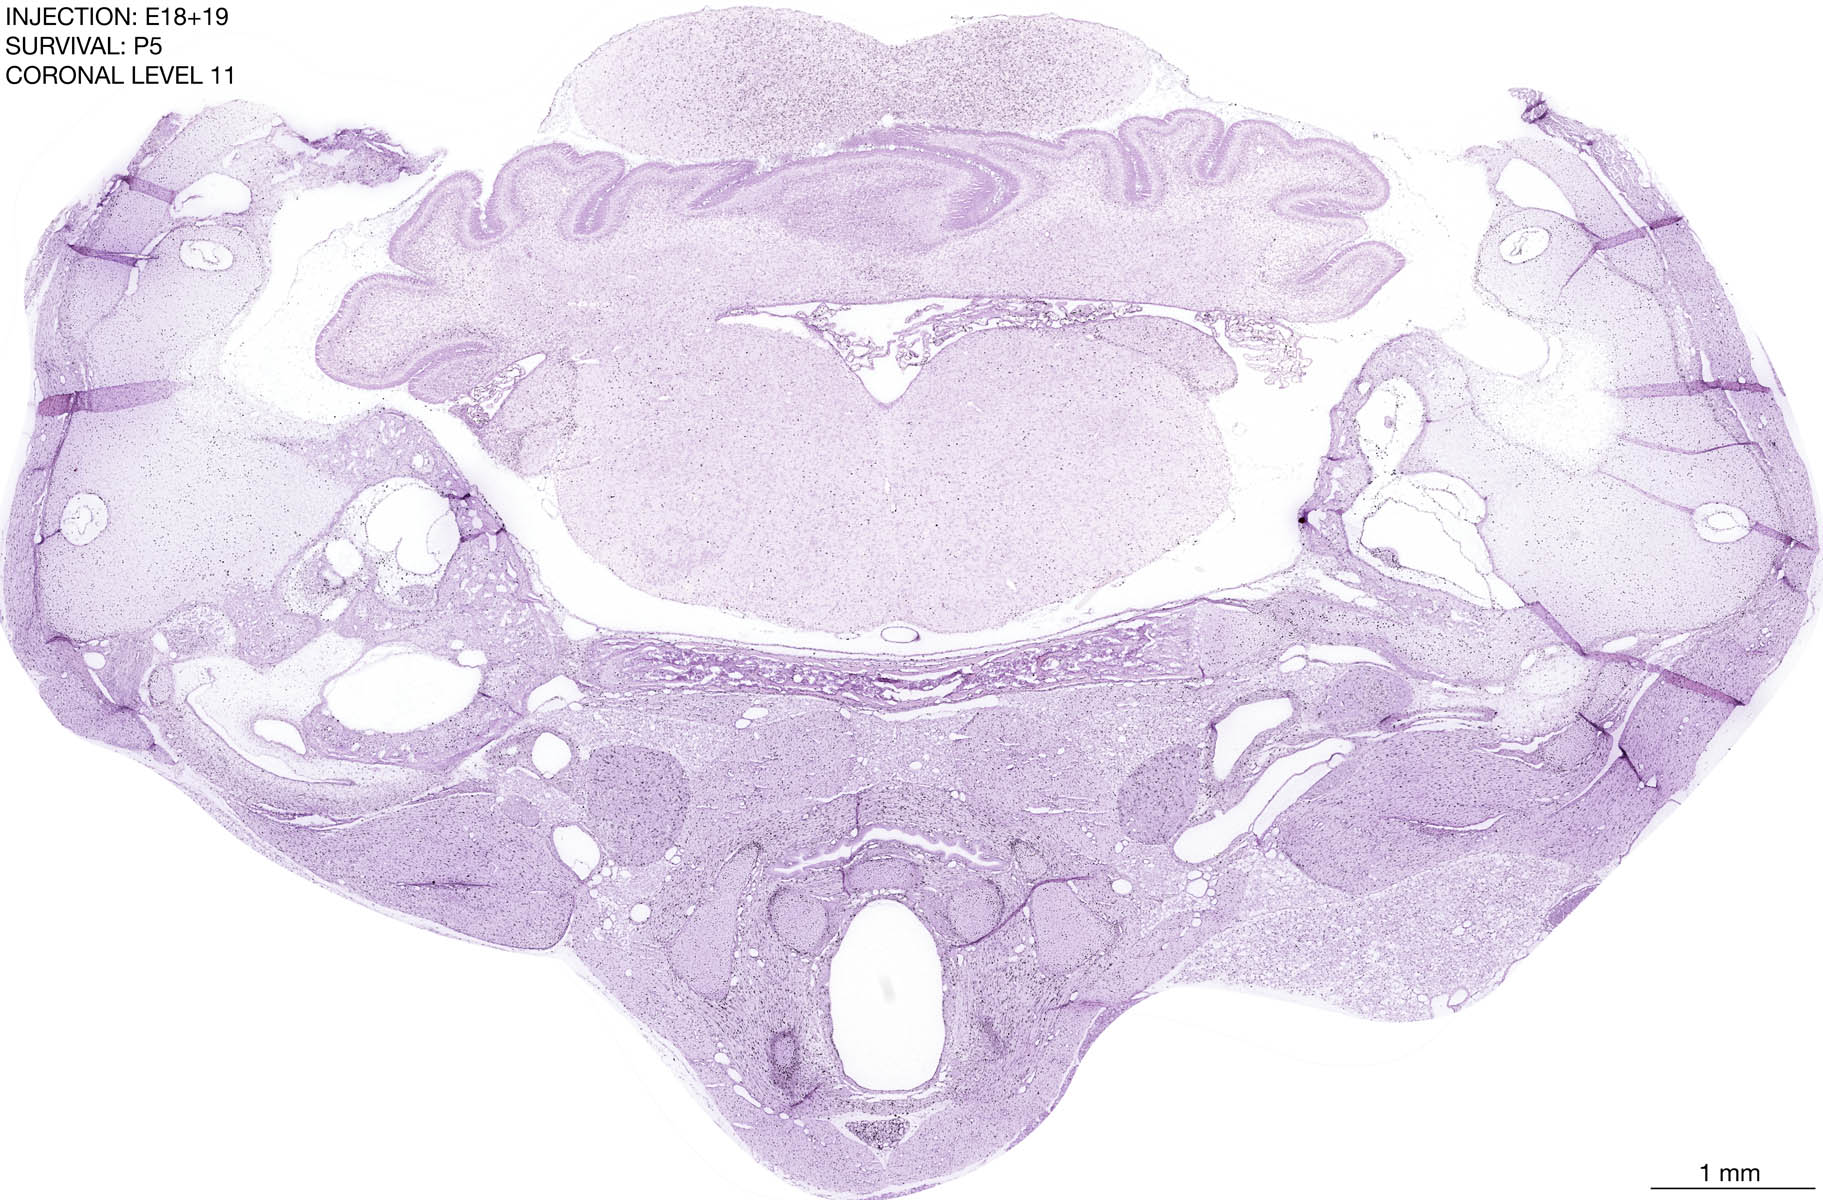

The images below are from the brain of a rat that was exposed to tritiated thymidine on E18+19 and survived to P5. Download: Large | High Res Download: Large | High Res Download: Large | High Res Download: Large | High Res Download: Large | High Res Download: Large | High Res Download: Large | High Res Download: Large | High Res Download: Large | High Res Download: Large | High Res Download: Large | High Res Download: Large | High Res Download: Large | High Res Download: Large | High Res Download: Large | High Res Download: Large | High Res Download: Large | High Res Download: Large | High Res Download: Large | High Res Download: Large | High Res Download: Large | High Res Download: Large | High Res Download: Large | High Res Download: Large | High Res